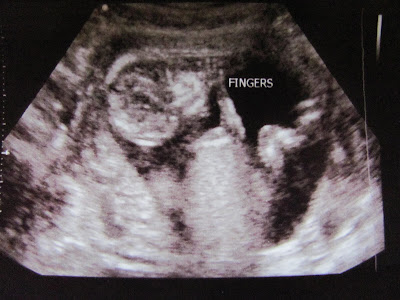

We had a sonogram today, due to the fact that I was measuring bigger than my week. It was so wonderful to see that sweet little adorable baby and hear the heartbeat. Everything looks great and we are so thankful and blessed to be carrying a baby. We are 14 weeks and the due date has been changed to Aug. 23.

Most beautiful sight ever! I love that baby so much already!